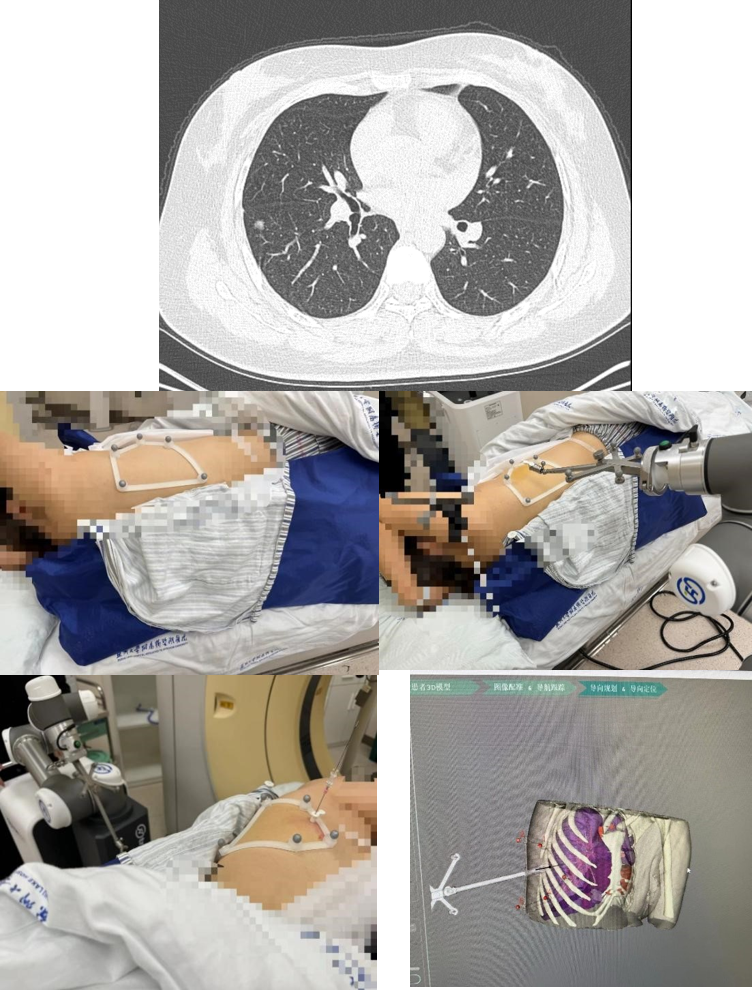

近日,一位来自省内的翟女士前来我院就诊。翟女士于三年前体检查时发现右下肺磨玻璃结节,初始大小5mm,定期随访观察。而近期在外院复查胸部CT时,翟女士发现右下肺结节较前逐步增大,现大小约8mm,且较前片对比实性成分稍增多。同时这次检查还发现右中肺近水平裂处见一枚新增的6mm磨玻璃结节,内可见空泡。为此,翟女士辗转多家医院就诊咨询,但提出的治疗方案翟女士始终不够满意。最后通过朋友介绍,翟女士找到我院胸心大血管外科专家马海涛教授。经过询问患者随访病史,结合影像表现,马海涛教授决定收治该名患者并为其手术。

患者右下肺大小8mm的混合磨玻璃结节位于背段气管以上肺组织外三分之一处;另右中肺大小6mm的磨玻璃结节位于水平裂边缘,且患者水平裂发育良好,可直接行右中肺结节楔形切除术。结合患者本人意愿,马海涛教授为其制定右中肺结节楔形切除术及右下肺结节定位后节段切除术的手术方案,精准定位及精准切除的同时,尽最大可能减少患者的肺功能损失。马海涛教授带领其团队充分讨论该患者的定位方案,决定使用“机器人穿刺导航定位系统”为该患者进行术前定位。该技术人机结合,通过病灶提取、路径规划、光学导航、穿刺实施等步骤完成术前定位工作,减少术中肺组织切除范围。相较于传统定位技术,该机器人定位系统在定位安全性、定位准确性、定位稳定性、定位效率上均有所提高,优势显著。

定位过程中,机器人快速的三位重建及路径规划步骤